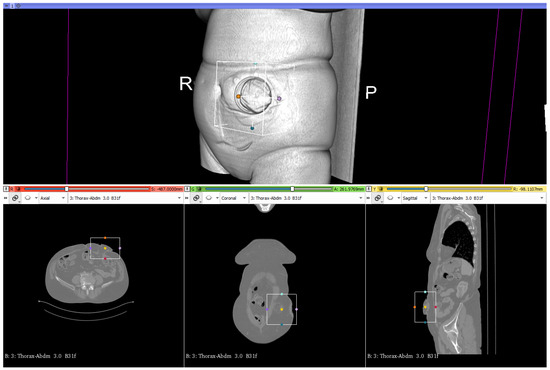

2.3.5. Processing of CT Scans and Design of the Ostomy Patch

2.4. Data Processing

2.4.1. Ostomy Surface Preparation